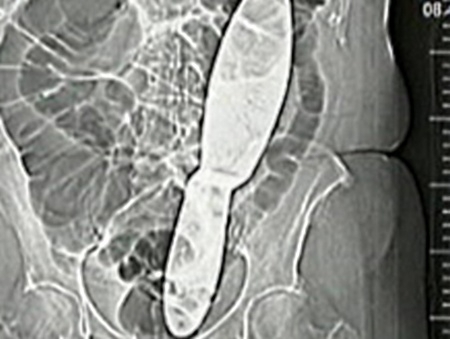

Imagem de raio-x mostra

Imagem de raio-x mostra "espátula" esquecida dentro de paciente na República Tcheca; mulher vai processar hospital

Uma mulher de 66 anos vai pedir uma indenização milionária a um hospital depois de encontrar um instrumento cirúrgico de 30 cm dentro do seu peito, em Ivancice, na República Tcheca.

Zdenka pediu um exame de raio-x, mas foi advertida que esse procedimento seria uma exposição desnecessária a radiação. Após muita insistência, um raio-x foi feito e uma espécie de espátula cirúrgica foi encontrada “perdida” dentro do seu abdômen.